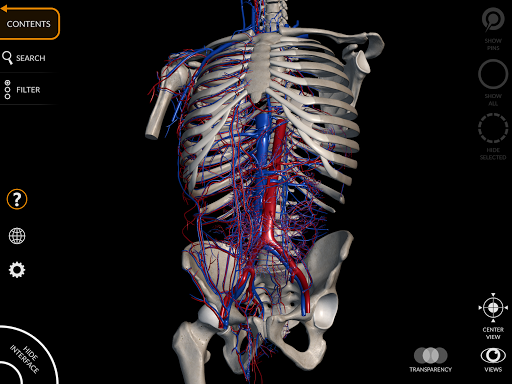

من خلال واجهة بسيطة وبديهية، من الممكن ملاحظة كل بنية تشريحية من أي زاوية.

تتميز النماذج التشريحية ثلاثية الأبعاد بتفاصيل خاصة ودقة تصل إلى 4K.

• الجهاز القلبي الوعائي

• تدوير وتكبير كل نموذج في مساحة ثلاثية الأبعاد

• وظيفة الشفافية